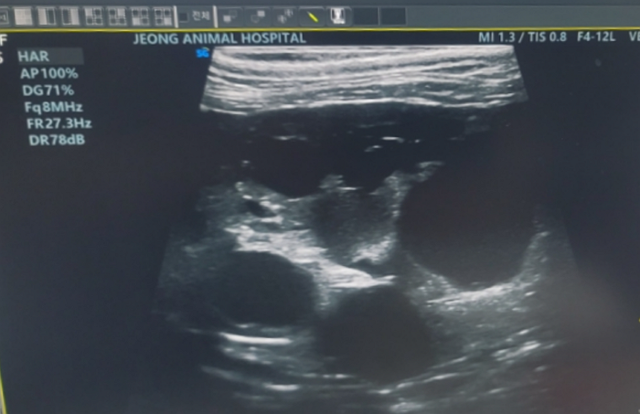

둘째 도도는 지난 2022년 다낭성 신장 질환(이하 PKD, 신장에 낭종이 생기는 유전성 질환)을 진단받았어요. 도도가 낳은 아깽이 8남매는 모두 입양 보냈었는데, 그중 '자반이' 집사님께 연락을 받았었죠. 자반이가 PKD 1기를 판정받았고, 이 질환이 유전성이라 어미냥인 도도도 PKD가 의심된다는 거였어요. 저는 도도의 새끼를 입양한 다른 집사님들께 모두 연락드렸습니다. 결과는 4마리가 PKD 진단 받았어요. PKD는 치료 방법이 없고, 당장 잘못되는 건 아니라 만성 신장병처럼 식단 관리를 통해 꾸준히 관리를 하며, 6개월마다 검진을 받아야 한다고 했습니다.

도도도 검사를 받아보고 PKD 확진을 받았어요. 그때 남편이 병원에 데려갔는데 진료 후 문자가 왔었죠.

도도도 PKD인데, 초음파 사진을 보는데 눈물 나더라.

충격받을까 봐 초음파 사진은 퇴근하면 보여줄게.

구멍이 너무 많고 심각하다고.

3개월마다 내원해 상황을 지켜보자네.

큰 병원으로 가는 것도 생각해 보라고 하셨어 .

이 문자를 받고 무슨 정신으로 근무한지 모르겠어요. 이후 원주에 있는 대형 동물병원을 방문했고, 검사 결과는 역시 좋지 않았어요. 혈액 검사 수치는 모두 정상인데, 낭종의 크기는 너무 컸습니다. 수의사 선생님은 이렇게 말씀하셨어요.

초음파 사진만 보았을 때는 PKD 고양이 중에

안 좋기로 원탑이지만,

혈액 검사 수치는 모두 정상인 걸 보면

이겨내고 있는 거예요.

아니 버티고 있죠.

정말 대단한 고양이예요.

6개월 후 재검을 진행했는데...PKD 진행 속도는 너무나 빨랐습니다. 일반적으로 PKD는 고양이가 7~8살 정도 됐을 때 발견되고, 진행이 빠르지 않아 1년에 한 번 정도의 검진을 하며 경과를 지켜본다고 해요. 도도는 보기 드물게 진행이 빠르다고 하셨어요. 다른 고양이와 비교하면 12살 수준의 고양이와 비슷하다고 하셨죠. 그 말을 듣는 순간 눈물이 쏟아졌지만, 꾹 참았습니다. 수의사 선생님은 안타깝지만 도도에게 남겨진 시간이 1~2년이라고 하셨어요.